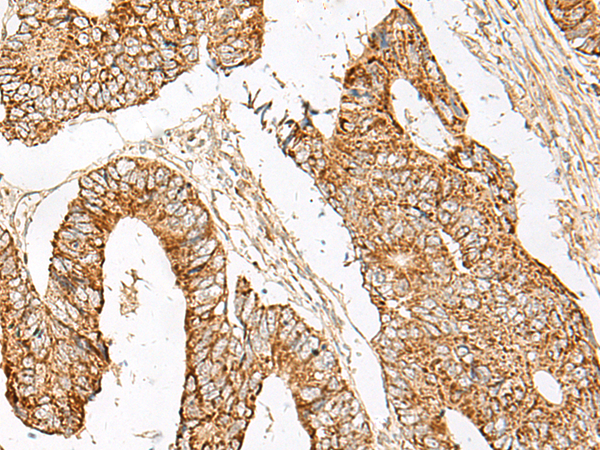

分类: 科研抗体货号: P13453别名: GCET1; SERPINA11; SERPINA11b应用: WB,IHC反应种属: Human